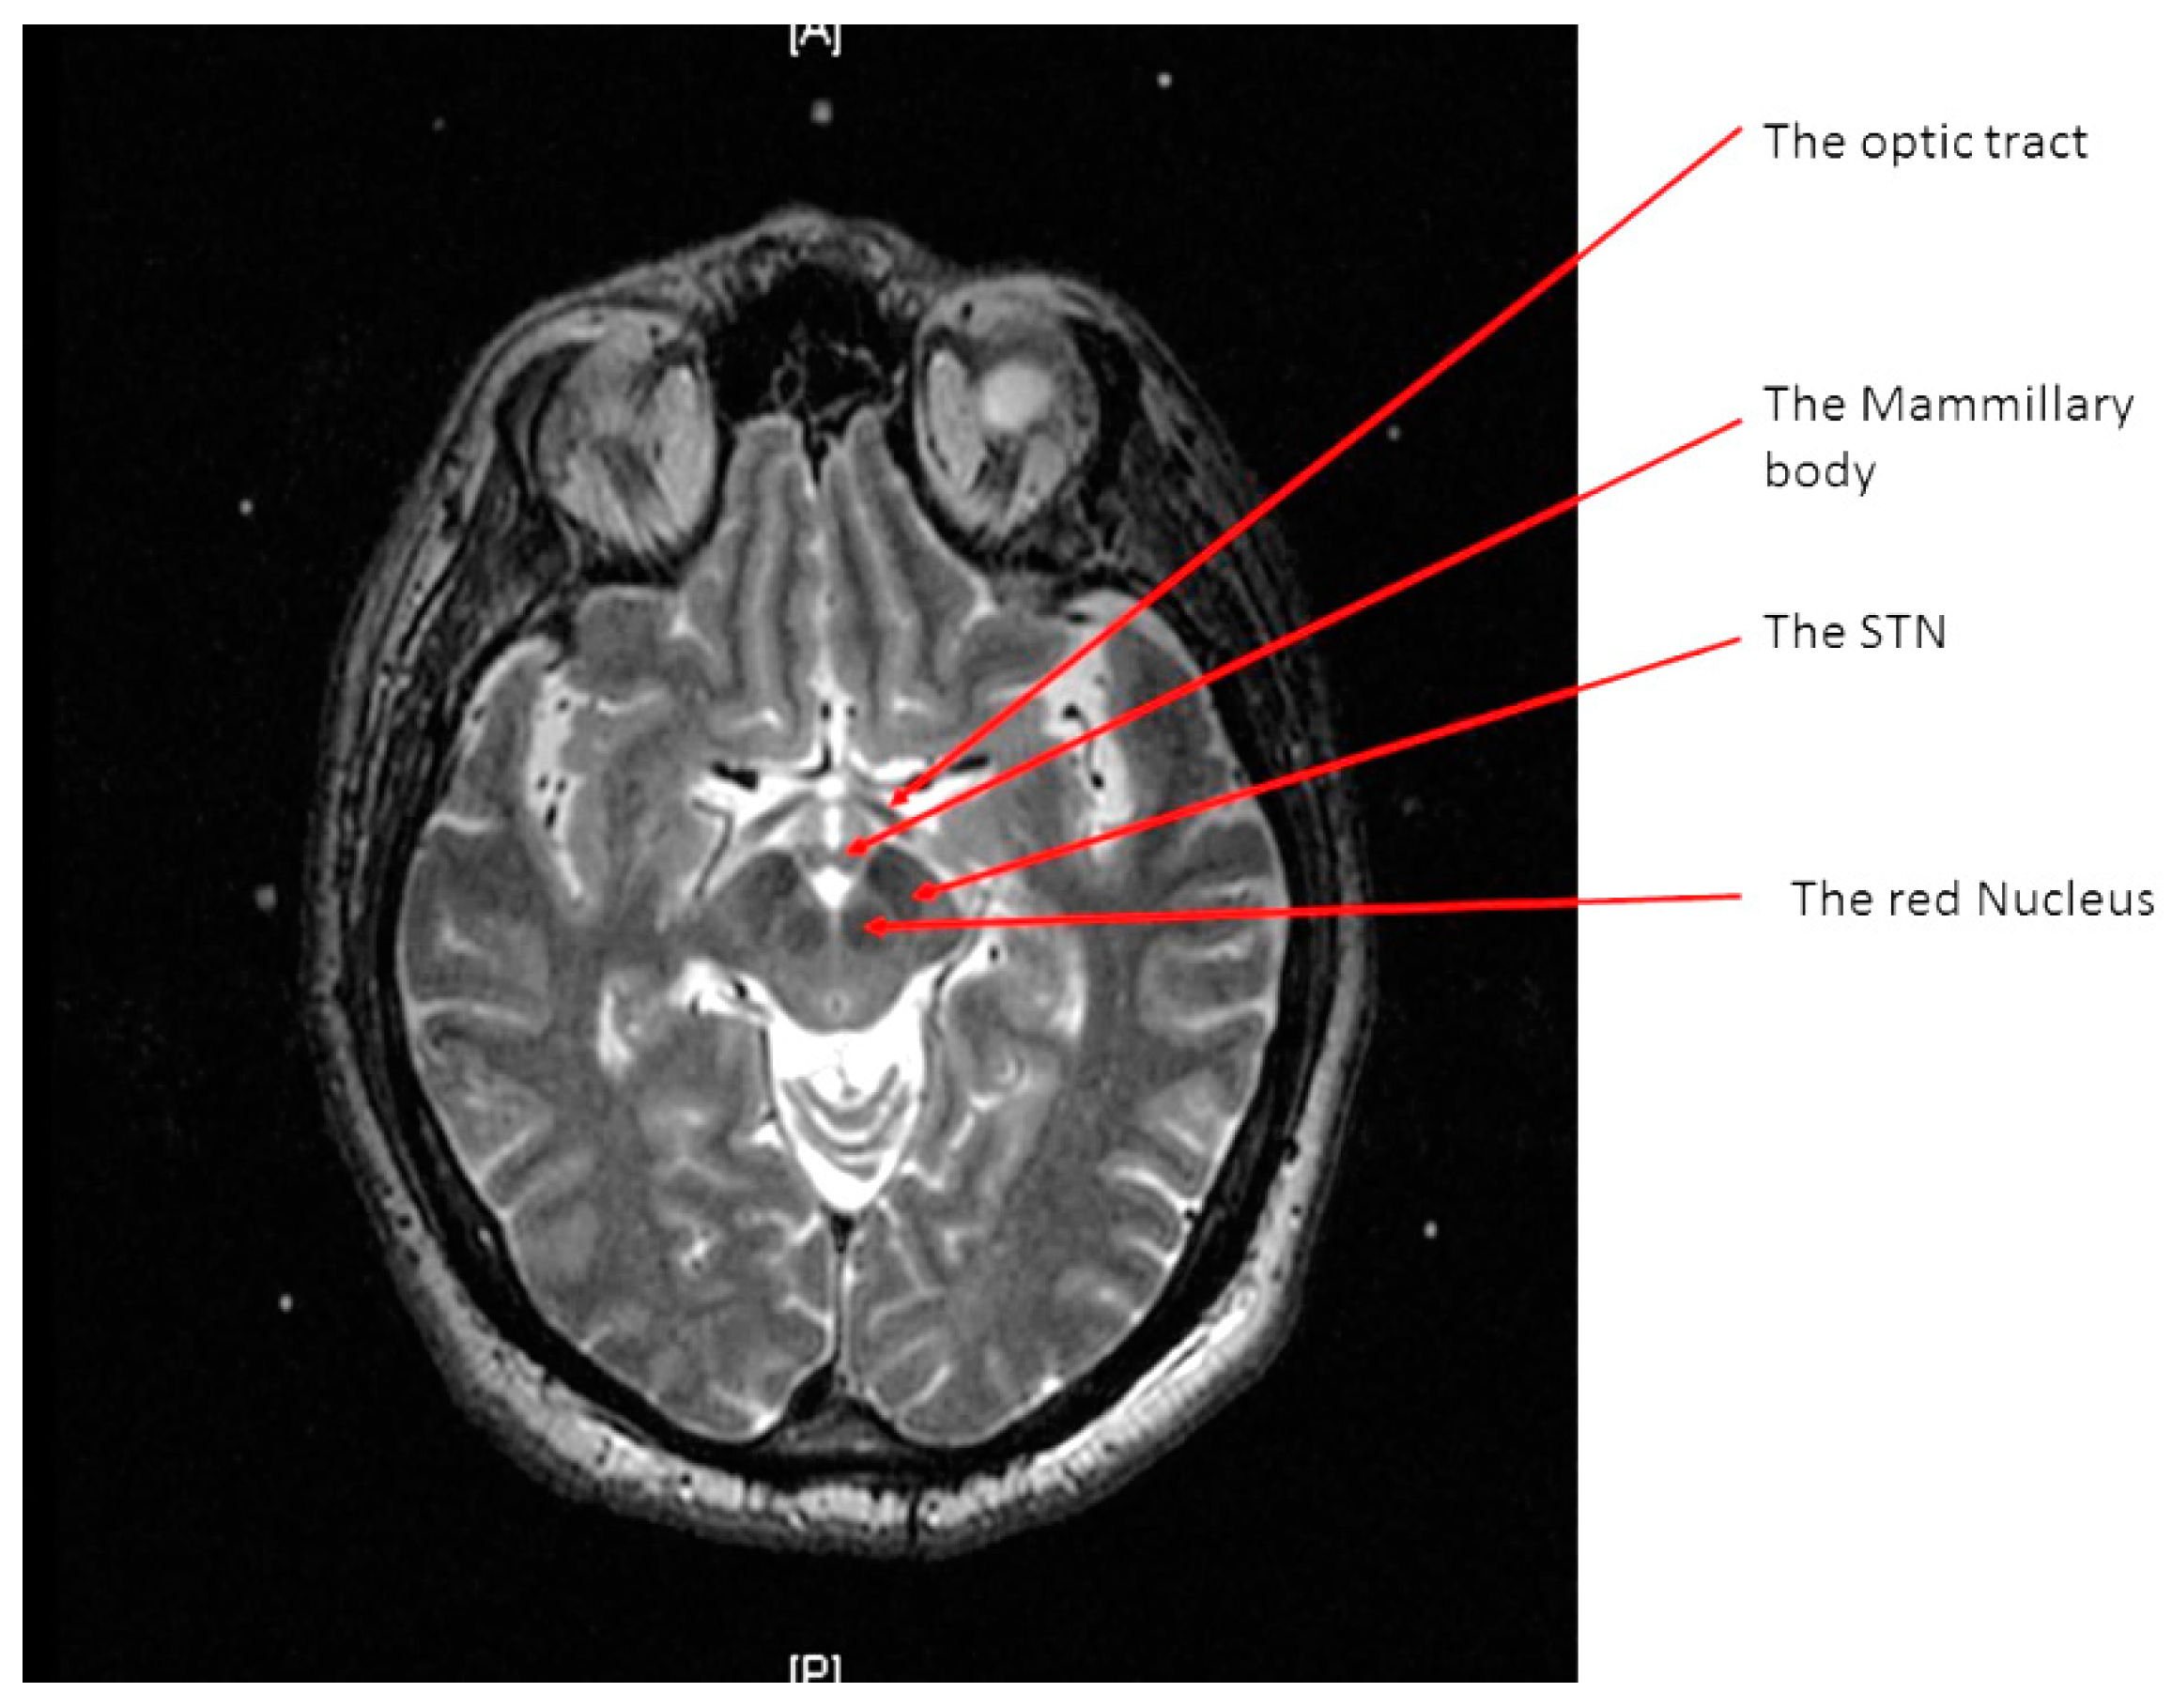

The STN is the hypointense structure located lateral and anterior to the red nucleus on axial T2 MRI (Figure 4) [8]. The center of the STN hypointensity was identified at the extension of a straight line drawn at the anterior margin of the RN bisecting the STN. Then, the coordinates were calculated using the same Excel worksheet.

Figure 4.

Calculating the subthalamic nucleus (STN) coordinates from the magnetic resonance imaging (MRI) console. (A) two diagonal lines intersecting at the center of the frame at the STN level with MRI coordinates of the center of the frame shown inside the red square; (B) a crosshair at the center of the left STN, with its MRI coordinates shown inside the red square, two line are drawn between the middle and lower fiducials on both sides of the frame and their lengths (in the blue rectangle) are used to calculate the Z coordinate; (C) a crosshair at the center of the right STN, with its MRI coordinates shown inside the red square, two line are drawn between the middle and lower fiducials on both sides of the frame and their lengths (in the blue rectangle) are used to calculate the Z coordinate.